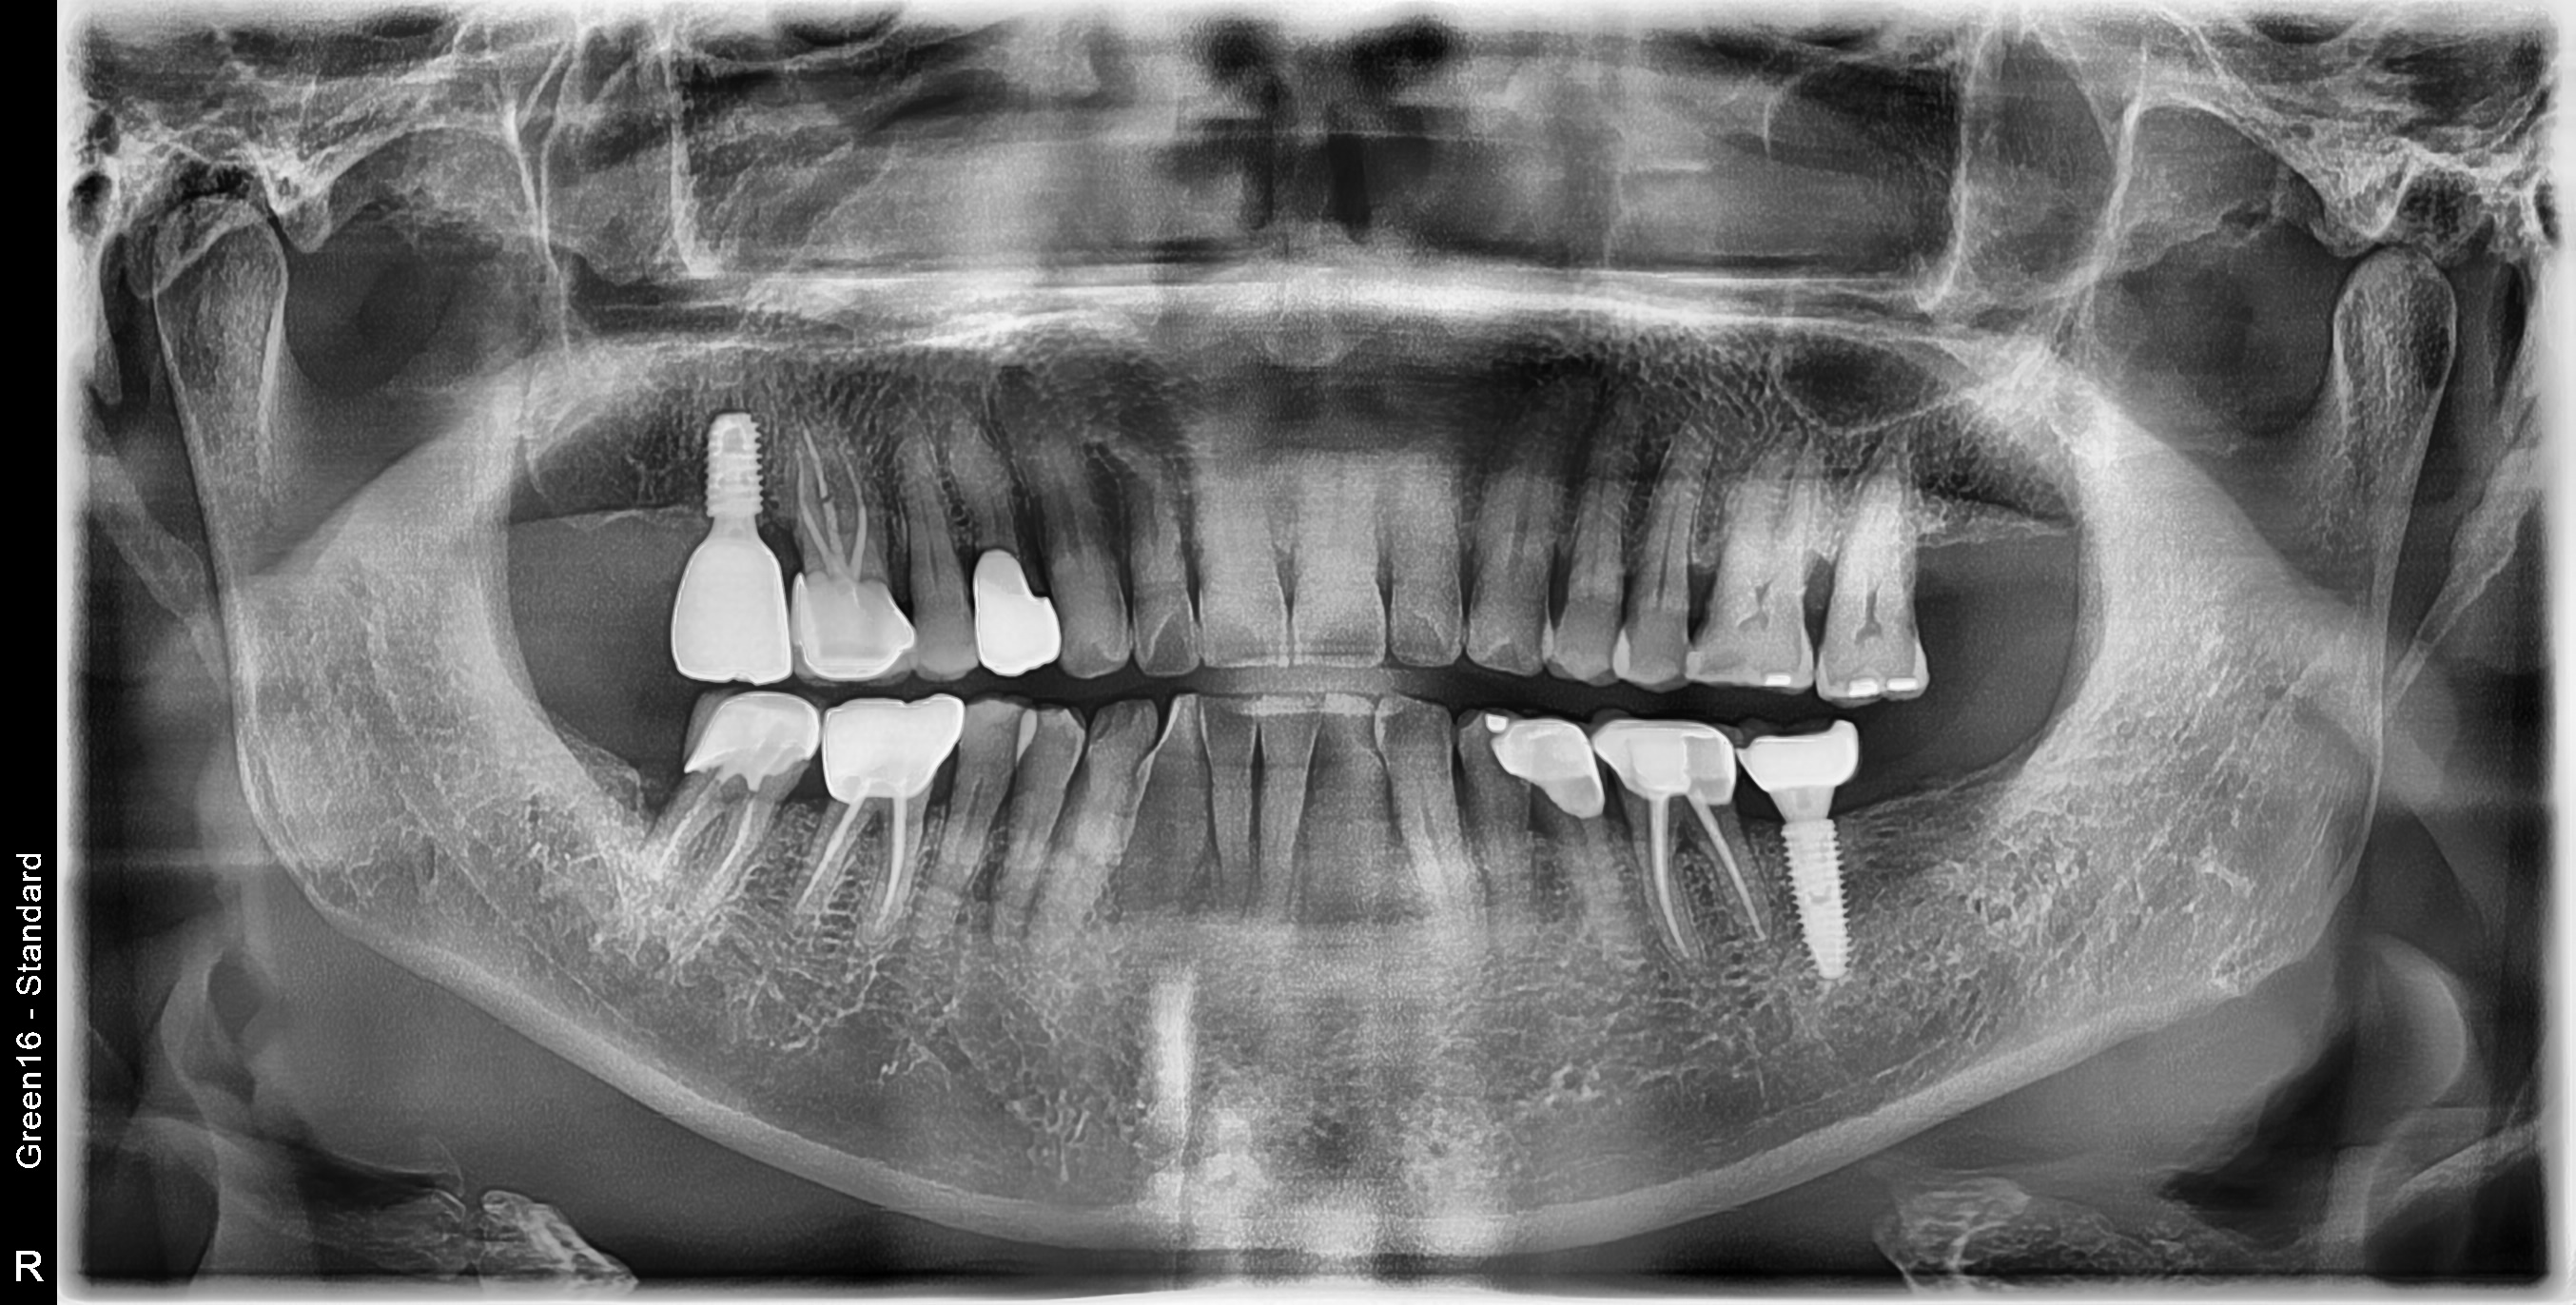

수술 전

수술 후

하악 임플란트 식립사례

전후사진